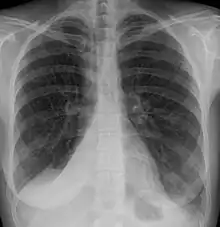

| Atelectasis of a person's right lung | |

Clinically significant atelectasis is generally visible on chest X-ray; findings can include lung opacification and/or loss of lung volume. Post-surgical atelectasis will be bibasal in pattern. Chest CT or bronchoscopy may be necessary if the cause of atelectasis is not clinically apparent. Direct signs of atelectasis include displacement of interlobar fissures and mobile structures within the thorax, overinflation of the unaffected ipsilateral lobe or contralateral lung, and opacification of the collapsed lobe. In addition to clinically significant findings on chest X-rays, patients may present with indirect signs and symptoms such as elevation of the diaphragm, shifting of the trachea, heart and mediastinum; displacement of the hilus and shifting granulomas.[10]